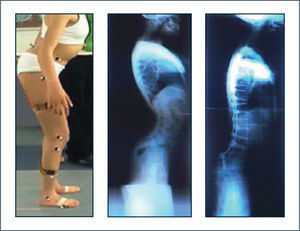

Marcha idiopática en punta de pies (idiopatic toe walking):Corresponde a una alteración de la marcha de etiología no precisada que se observa en niños neurológicamente sanos, sin antecedentes clínicos y con desarrollo psicomotor dentro de límites normales (17,18). La adquisición de la marcha ocurre a edad normal, pero presenta patrón en punta de los pies desde el inicio y se mantiene más allá de los 3 años de edad. Generalmente se asocia grado variable de acortamiento del tendón de Aquiles y son capaces de corregir su patrón de marcha en forma espontánea si se les solicita hacerlo. Lo anterior da cuenta de un control motor preservado, constituyendo una característica diferencial importante con respecto a otras patologías. Uno de los diagnósticos diferenciales principales es la parálisis cerebral tipo diplejía espástica en su forma leve.

Varios autores han utilizado el análisis de marcha para describir la marcha idiopática en punta de pies y realizar el diagnóstico diferencial con la parálisis cerebral. Hicks y cols (19) describieron el patrón kinemático de un grupo de niños portadores de marcha idiopática en punta de pies y los compararon con un grupo de niños con parálisis cerebral. Las alteraciones principales fueron observadas a nivel de los tobillos, caracterizada por un aumento de flexión plantar durante las fases de apoyo y balanceo. La kinemática a nivel de la rodilla mostró un comportamiento diferente en ambos casos, determinado por tendencia a la hiperextensión de la rodilla durante la fase de apoyo en la marcha idiopática en punta de pies, mientras que en los casos de parálisis cerebral el hallazgo predominante era flexión a este nivel durante la misma fase. Kelly y cols (20) describió comportamiento dentro de límites normales del punto de vista kinemático a nivel de rodillas en niños con marcha idiopática, mientras que los niños con parálisis cerebral leve mostraban frecuentes alteraciones kinemáticas en el plano sagital. Adicionalmente destacó hallazgos característicos a nivel de tobillos durante la fase de balanceo caracterizados por incursión normal hacia la dorsiflexión en el balanceo inicial y medio para favorecer el avance del pie, no obstante hacia el final de esta fase se observaba una desviación hacia la flexión plantar que era mantenida hasta el siguiente contacto inicial, realizando el contacto con el piso con el antepie. Westberry y cols (21) estudiaron 51 niños con diagnóstico establecido de marcha idiopática en punta de pies con el fin determinar los hallazgos kinemáticos y kinéticos y comprobar en forma objetiva si estos pacientes lograban efectivamente corregir su patrón de marcha en forma voluntaria. Como resultado lograron identificar características diferenciales evidentes en la marcha niños con marcha idiopática en puntas v/s portadores de parálisis cerebral, a la vez que hicieron evidente la capacidad de corregir parámetros kinemáticos y kinéticos de la marcha a demanda en la mayoría de los niños con esta alteración. Algunos investigadores han utilizado el análisis de marcha para objetivar perfil temporal de la alteración, hasta la edad adulta, incluyendo casos de evolución espontánea y otros sometidos a diferentes tratamientos ya sea conservadores o quirúrgicos mediante alargamiento de flexores plantares (18,22–25). De este modo ha sido posible establecer la evolución satisfactoria del cuadro en la mayoría de los casos.

Alvarez y cols (8) propuso una clasificación de la marcha en niños con marcha idiopática en punta de pies basada en parámetros kinemáticos y kinéticos del laboratorio de marcha, estableciendo diferentes grados de severidad de la alteración y alternativas terapéuticas en cada caso. Si bien no es una clasificación ampliamente aceptada es una buena aproximación objetiva al problema.

En suma el análisis instrumentado de la marcha permite establecer las alteraciones de la marcha en los niños portadores de marcha idiopática en punta de pies, establecer nivel de severidad de la alteración, realizar seguimiento en el tiempo y establecer diagnóstico diferencial con otras patologías, principalmente con la parálisis cerebral.